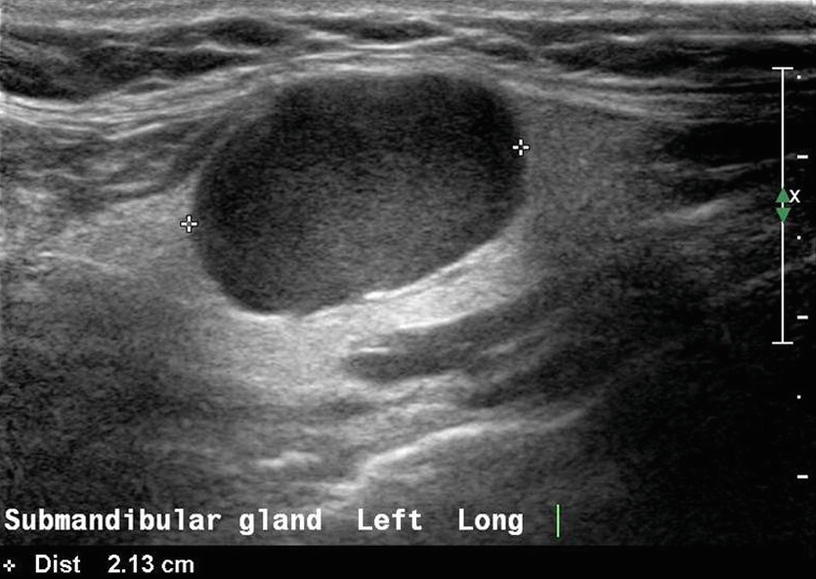

Diagnostic Work Up In Obstructive And Inflammatory Salivary Gland Disorders Abstract Europe Pmc, They are the largest of the salivary glands. In humans, the two parotid glands are present on either side of the mouth and in front of both ears. The parotid glands are superficial structures and are readily amenable to high resolution ultrasound examination. The patient can sometimes palpate a stone under the mandible.the stone can block the duct causing infection and. Chronic obstruction can cause infections. The child had earlier episodes of pain and swelling in this region. Differentiate possible benign from malignant neoplasms; U/s of the parotid gland protocol. Each parotid is wrapped around the mandibular ramus. Intraglandular and extraglandular lesions to be localised and differentiated. These ultrasound images suggest right parotid abscess. The left parotid gland appears note also the dilatation of the intraglandular part (within the submandibular gland) of the wharton duct. The patient can sometimes palpate a stone under the mandible.the stone can block the duct causing infection and swelling. The parotid gland is a major salivary gland in many animals. A lump in the gland/neck.